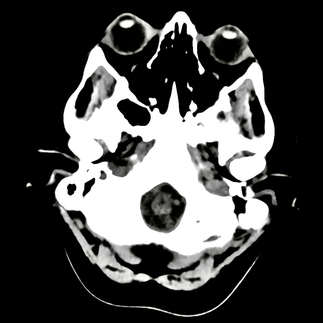

Our unique designs feature actual CAT scan photographs from our founder's CT scan, capturing the real, raw visual of what battling mental health struggles can look like.

Key Features: Authentic Imagery: Each piece in this collection showcases genuine CAT scan images of the brain, offering a stark, honest portrayal of the neurological impact of depression. These images are sourced directly from our founder’s personal CT scans, underscoring the reality of mental health challenges.